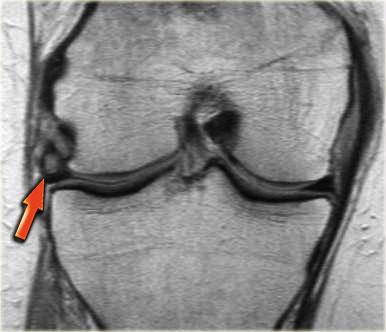

Bên trái là một trường hợp khác của sụn chêm ngoài bị lật.

- Lưu ý sừng trước rất lớn.

Phần trong là sừng sau đã bị di lệch. - Phần trong chạy vào hố gian lồi cầu.

- Phần bị di lệch được nhìn thấy rõ ràng như là ‘cấu trúc thứ ba’

trong hố gian lồi cầu. - Điểm nối với phần còn lại của sừng sau.

- Điểm nối với phần còn lại của sừng sau.

- Phần còn lại rất nhỏ của sừng sau.